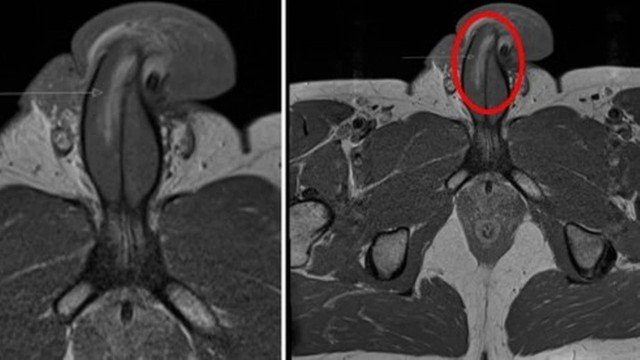

Homem fratura pênis verticalmente no sexo, em 1º caso da história